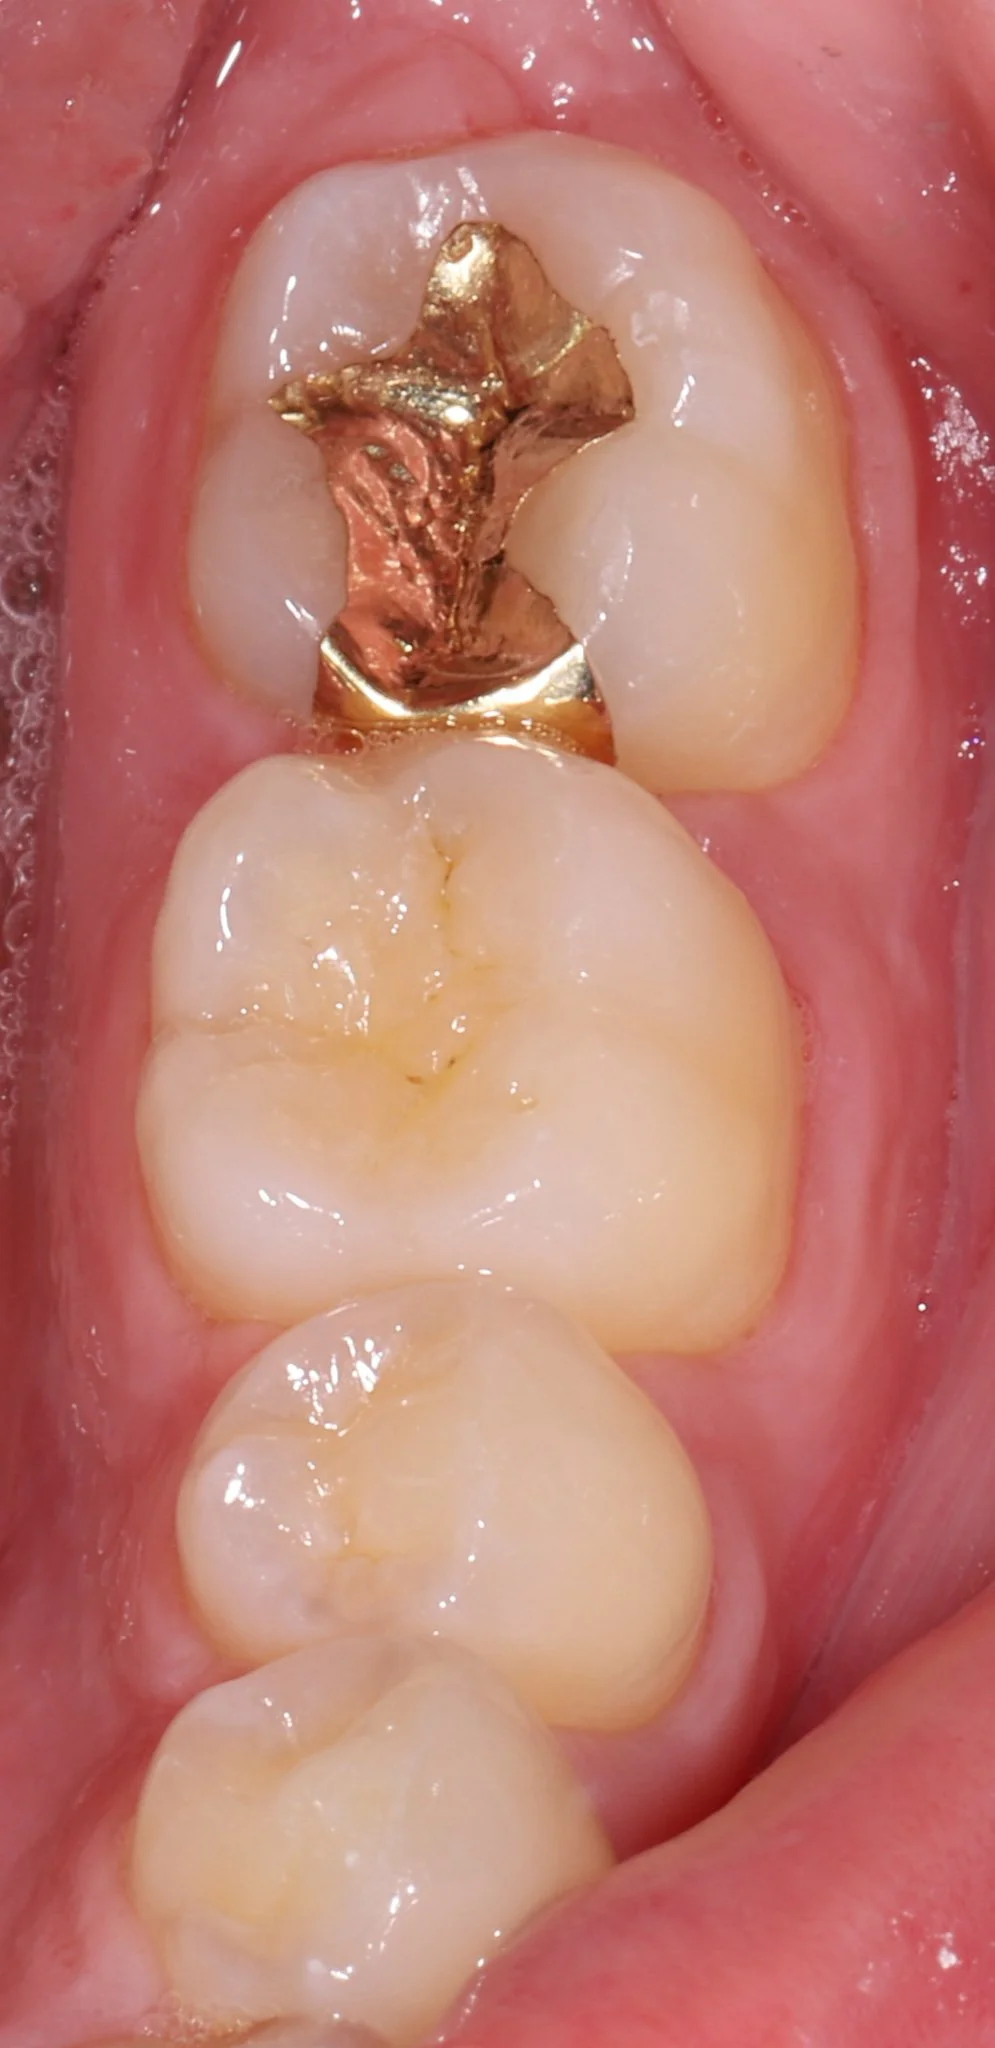

Close-up of the lower molars in a person's mouth, showing a gold dental filling on the bottom molar and the other teeth are natural and clean.

Gold Restoration

Gold Onlay

Gold Inlay on a molar

Gold Inlay